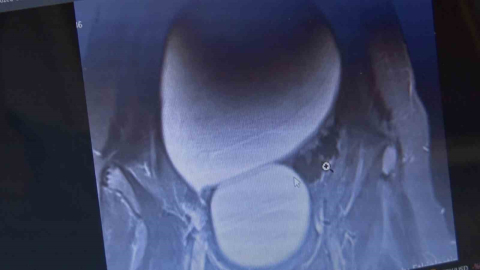

Sivas’ta yaşayan 12 yaşındaki genç kızın karın bölgesinde bulunan kavun büyüklüğündeki kist başarılı operasyonla çıkarıldı.

Sivas’ta yaşayan 12 yaşındaki N.B. şiddetli karın ağrıları ve düzensiz adet kanamaları şikayetiyle hastaneye başvurdu. Yapılan detaylı tetkikler sonucunda genç kızın karın bölgesinde yaklaşık 25 santimetre çapında adeta kavun büyüklüğünde bir kist olduğu tespit edildi. Medicana Sivas Hastanesi’nde Çocuk Cerrahisi Uzmanı Op. Dr. Mahmut Aluç tarafından gerçekleştirilen başarılı bir operasyonla, genç kızın sol yumurtalığında bulunan ve karaciğere kadar uzanan devasa kist içerisindeki 1.6 litre su boşaltılıp, başarıyla çıkarıldı. Sağlığına kavuşan genç kız taburcu edildi.

Operasyon sırasında kistten yaklaşık 1.6 litre sıvı boşaltıldı

Çocuk Cerrahisi Uzmanı Op. Dr. Mahmut Aluç, kisttin içerisinden yaklaşık 1.6 litre sıvı boşaltıldığını söyleyerek, “ Karın ağrısı, düzensiz adet şikayetiyle bize geldi. Dışarıda yapan tetkiklerde ve bizde yapılan tetkiklerinde karın içerisinde yaklaşık yirmi beş santimetrelik çapında bir kitli kitle tespit ettik. Burada da tetkiklerimize tekrar baktığımızda sol över kökenli bir kisttik yapı olduğunun farkına vardık. Gerekli incelemeleri yaptıktan sonra ve ailenin onayını aldıktan sonra hastayı operasyona aldık. Karaciğere kadar uzanan bir kisttik yapımız vardı. Onun içerisinde yaklaşık 1.6 litre sıvı boşalttık. Over dokusunu, yumurtalık dokusunu koruyarak kisti tamamen eksize ettik. Hastamızı şifayla taburcu ettik. Patoloji sonucumuz da iyi huylu olarak geldi” dedi.